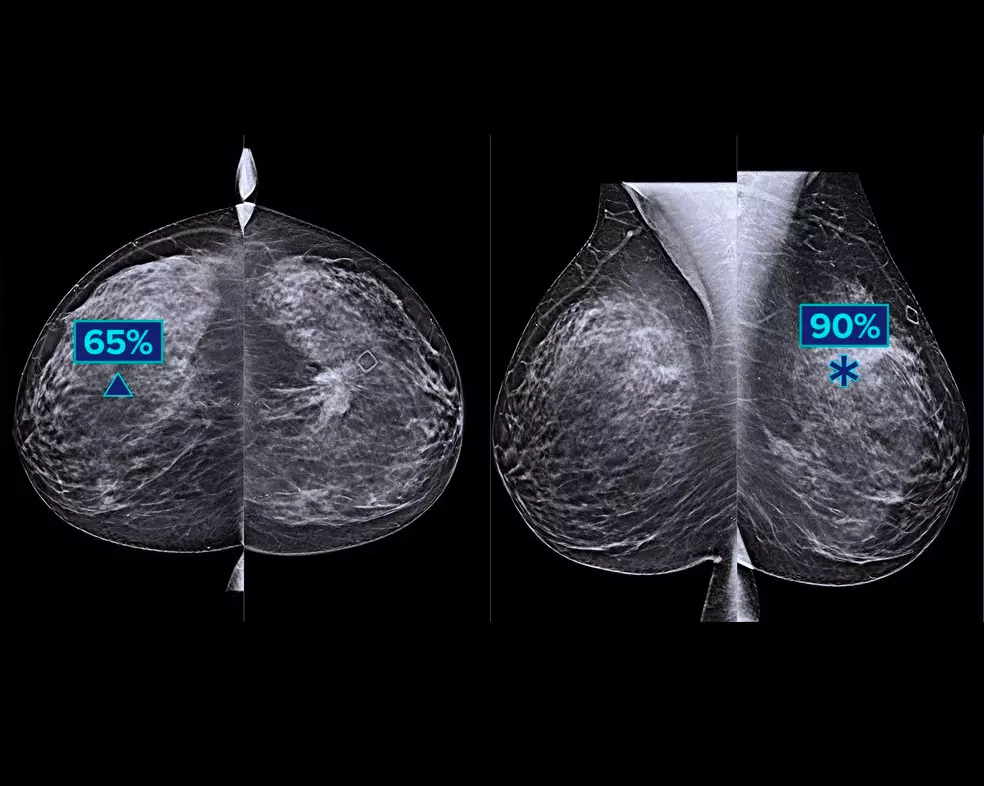

Die intelligent 2D-Bildgebungstechnologie erzeugt mittels KI-Unterstützung robuste und dennoch natürlich aussehende, synthetische 2D-Bilder in Korrelation mit den 3D-Mammografiedaten. Dies ermöglicht Radiologen eine schnelle und zuverlässige Erkennung kleinster mammografischer Charakteristika und der Läsionsmorphologie.*

Mehr klinisch relevante Details aus hochauflösenden 3D-Mammografiedaten. Nutzen Sie KI-gestützte Analysen zur sicheren Visualisierung von feinen Gewebemerkmalen und Läsionen in den rekonstruierten, synthetischen 2D-Aufnahmen.

• Herausragender 2D-Bildkontrast mit besserem Hintergrund und lokalisierter Dichte für eine FFDM-ähnliche Darstellung von Parenchymgewebe.